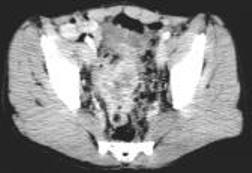

病历摘要:男,54岁病史:间歇性肉眼血尿伴下腹部隐痛7月余。为全程血尿,浓茶色,并有尿频尿急尿痛。当地医院曾造影检查示“膀胱结石”,入院前3天当地医院检查示“膀胱肿瘤”体查:心肺腹无明显阳性体征,双肾区无叩痛,双输尿管行程无压痛点,膀胱区未见肿胀、隆起实验室检查:尿常规:淡黄色,混浊,潜血大量,镜检白细胞370/μl(↑)